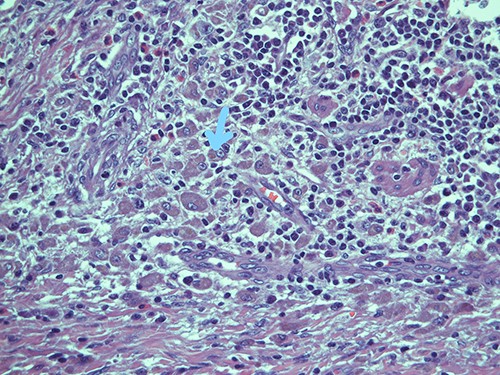

On microscopy, the appendix showed a thickening of his walls due to an accumulation of rounded elements with rich granular cytoplasm containing amorphous corpuscles and surrounded by microcalcifications, macrophage elements with adjacent de-epithelialized, ulcerated and eroded mucous tracts. No positive S100/pancytokeratin elements were found in the numerous sections examined. The morphological findings therefore indicated a form of malakoplakia (Figs 1–3), confirming its non-eptheliod and non-neoplastic nature (Fig. 4).

Intracellular and extracellular Michaelis–Gutmann bodies surrounded by inflammatory cell infiltrate of histiocytes; haematoxylin and eosin, magnification ×40.